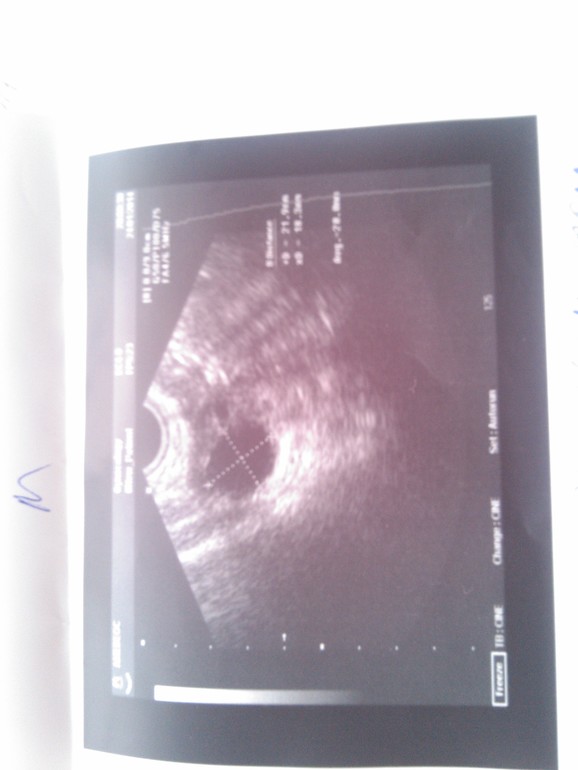

Девочки очень нужен ваш совет или комент))Ситуация такая: на 12 ДЦ делаю первый тест на О (Вандер тест),показывает бледную вторую полоску, в этот же день вечером иду на узи, результат Доминантный фолликул 20 мм, эндометрий 12 мм, врач говорит вот вот будет овуляция. Приехала домой решила сделать тест, полоска такая же бледная,после этого каждый день делала тесты,фото прилагаю. Когда была О? На тесты клей немного попал.Цикл в среднем 29 дней, сегодня 15 ДЦ